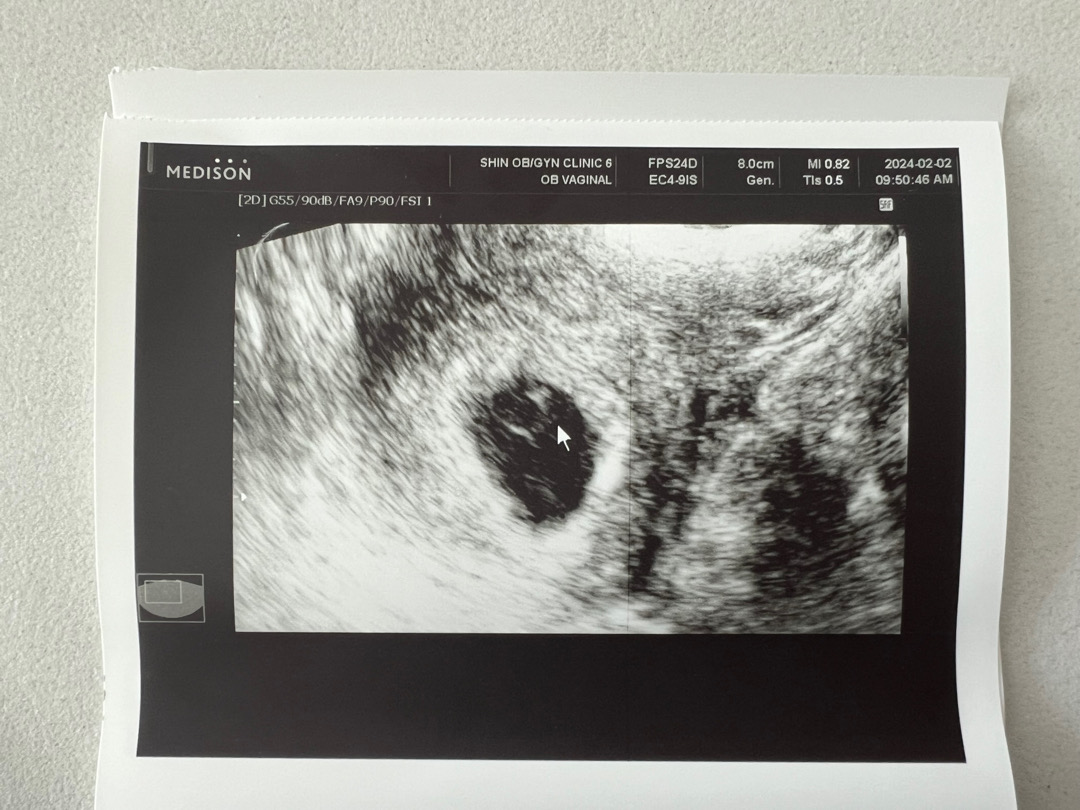

얼마전에 파이널 진하기 변화가 더디다고 괜한 걱정에 엉엉 울었다가 오늘 병원가서 난황이랑 아기도 잘 있고, 아직 너무 쪼꼬매서 잘 들리진 않았지만 콩, 콩, 콩 하는 심장소리도 듣고왔어요!! 그거보고 또 오열ㅠㅠㅠㅠ 눈물만 많아지는 것 같아요ㅠㅠㅋㅋㅋㅋ 2주 후에 오라시는데.. 1주도 길었는데 2주는 어떻게 버티지 싶어요..! 제발 그때까지 건강하게만 잘 있어주길 ㅠㅠ!!!!😭

네이버 주수 계산으로는 6주 4일차예요! 근데 아기가 제대로 보이면 크기보고 주수는 다시 알려주시겠다고 하셔서 좀 줄어들 수 있을 것 같아요!!